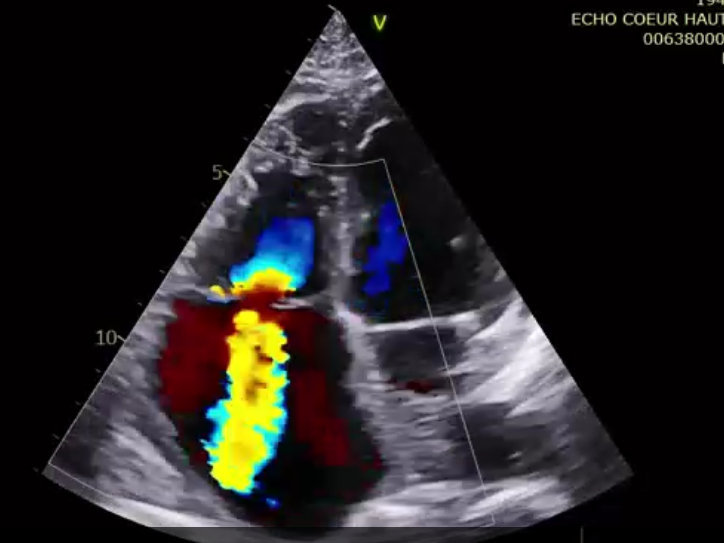

術前超聲提示大量三尖瓣反流

術后超聲提示微量瓣周漏